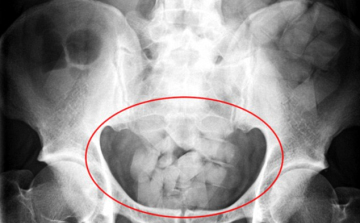

Mintegy 13 millió forint értékű kokainnal a gyomrában próbált meg bejutni az országba egy venezuelai nő, akit a NAV pénzügyőrei feltartóztattak a Liszt Ferenc-repülőtéren - közölte a NAV hétfőn az MTI-vel.

Szüret: húsz kiló kokain Ferihegyen

Húszkilónyi, háromszázmillió forint értékű kokaint foglaltak le a pénzügyőrök a budapesti Liszt Ferenc repülőtéren - tájékoztatta a Nemzeti Adó- és Vámhivatal (NAV) kedden az MTI-t.